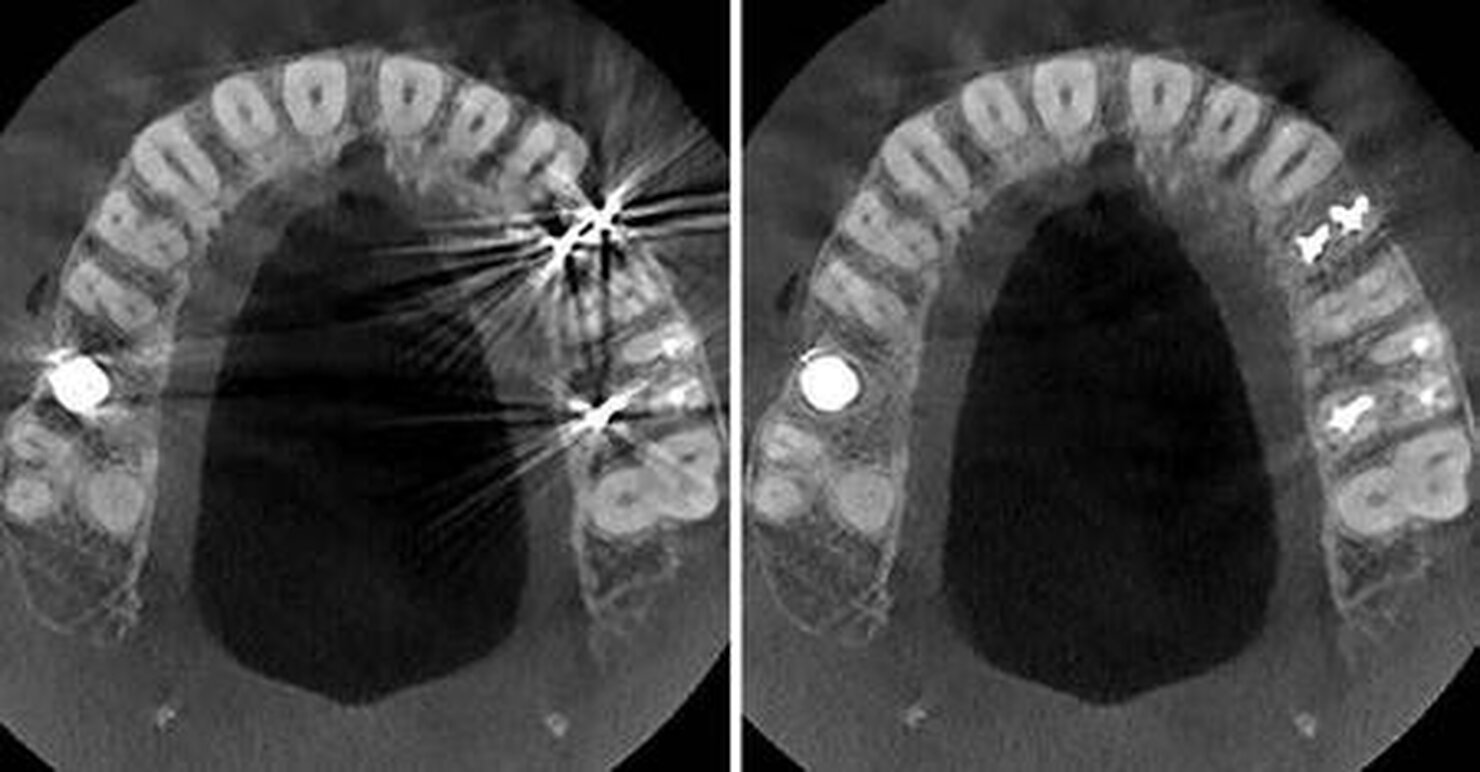

L’esclusiva tecnologia CS MAR con confronto dinamico riduce automaticamente gli artefatti da parti metalliche, aiuta a confermare la diagnosi e riduce il rischio di errori d’interpretazione.

Tecnologia CS MAR1

CS MAR permette una riduzione significativa degli artefatti causati da impianti, otturazioni e protesi.